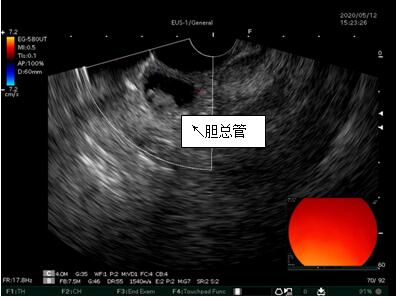

69歲王姓患者,因“發(fā)現(xiàn)無(wú)痛性黃疸1月”入院,根據(jù)患者病史,患者診斷傾向于壺腹部腫瘤所致梗阻性黃疸。予以完善腹部CT及上腹部MRI加MRCP均顯示肝內(nèi)外膽管擴(kuò)張,未發(fā)現(xiàn)明顯膽管,胰腺及十二指腸乳頭部腫瘤,且患者CA199正常。以前醫(yī)院未引進(jìn)超聲內(nèi)鏡,這類(lèi)患者到此就遇到診斷瓶頸。此患者經(jīng)過(guò)消化內(nèi)科張丹霞副主任醫(yī)師完善超聲內(nèi)鏡檢查后,可以清楚顯示膽總管下段壁內(nèi)軟組織占位。患者通過(guò)超聲內(nèi)鏡檢查診斷明確,轉(zhuǎn)至肝膽外科行手術(shù)治療。

超聲胃鏡圖片

膽總管小腫瘤性病變CT及MRI檢查陽(yáng)性率偏低,因其低代謝特征,PET-CT陽(yáng)性率也偏低,超聲內(nèi)鏡對(duì)這類(lèi)疾病的診斷陽(yáng)性率是所有檢查中最高的,且可行穿刺活檢進(jìn)一步確診病灶性質(zhì)。

環(huán)掃超聲內(nèi)鏡主要用于胃腸道粘膜下腫物診斷,胃腸道腫瘤分期,發(fā)現(xiàn)早期胃癌等,扇掃超聲內(nèi)鏡主要用于診斷膽道及胰腺疾病,并且可行穿刺活檢取病理。